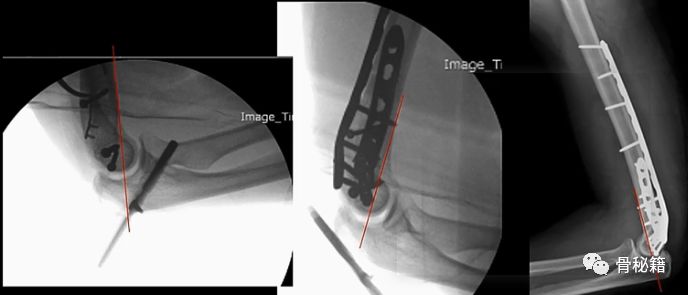

术中透视及体位,最常用的侧卧,如下图,

该体位下的透视,正位

侧位

铺单后的体位图

该例患者的前倾角就没有较好的恢复

3.术中如何保证恢复呢和判断呢?

在肱骨前方画一条线,看看该线的位置,是否经过滑车的中心,如果经过则说明复位较好。